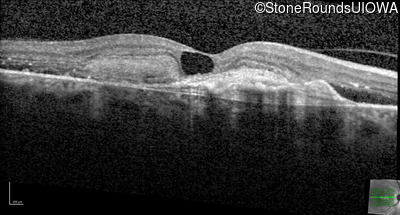

AR Stargardt Disease (IIA)

Age at visit: 59 years (Visit 3)

This 59 year old woman first noticed vision loss in her right eye a few months earlier. She has a cousin with Rhodopsin-associated RP.

Diagnosis & molecular findings

Disease Gene Allele 1 variant(s) Allele 2 variant(s) Inheritance mode

AR Stargardt Disease ABCA4 Arg219Thr AGA>ACA Gly863Ala (G)GA>(G)CA AR